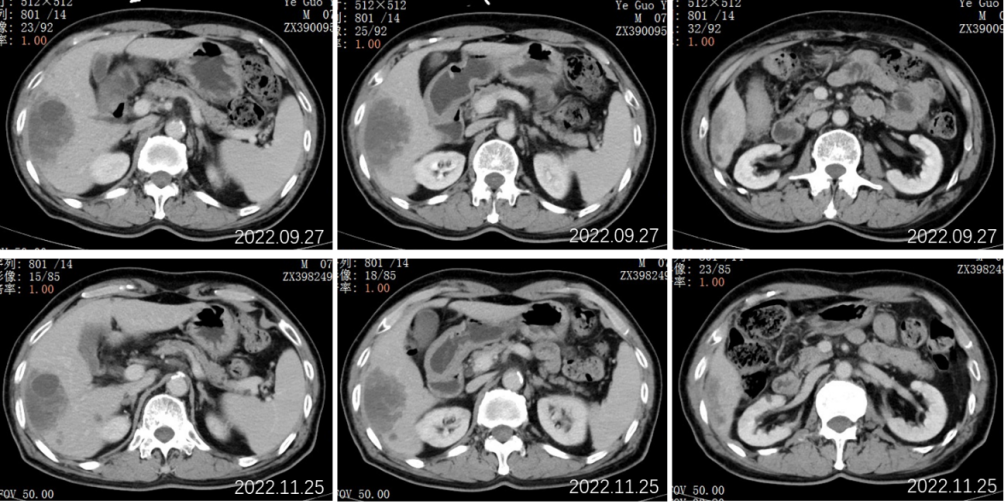

2022.09.27腹部CT增强:肝胆管细胞癌治疗后复查:1、肝右叶多发占位,较前大小相仿,目前仍可见活性;2、肝内及双肾多发小囊肿,相仿;肝S2段小血管瘤考虑,相仿;3、慢性胆囊炎改变;4、肝内钙化灶;前列腺钙化灶。

2022.11.25腹部CT增强:肝胆管细胞癌治疗后复查:对比2022-09-27日:1、肝右叶多发占位,较前大小相仿,目前仍可见活性;2、肝内及双肾多发小囊肿,相仿;肝S2段小血管瘤考虑,相仿;3、慢性胆囊炎改变;4、肝内钙化灶;前列腺钙化灶。

2023.5.28腹部CT增强:肝胆管细胞癌治疗后复查:对比2022-11-25日:1、肝右叶多发占位,较前相仿;2、肝内及双肾多发小囊肿,肝S2小血管瘤,大致相仿;3、慢性胆囊炎改变;胆囊内点状结石未见显示;4、肝内钙化灶;前列腺钙化灶。

2023.09.29腹部增强CT:肝胆管细胞癌治疗后复查:对比2023-05-28日:1、肝右叶多发占位,较前大致相仿;2、肝内及双肾多发小囊肿,肝S2小血管瘤,大致相仿;3、慢性胆囊炎改变;胆囊周围渗出,较前稍增多;4、肝内钙化灶;前列腺钙化灶;新见盆腔少量积液。